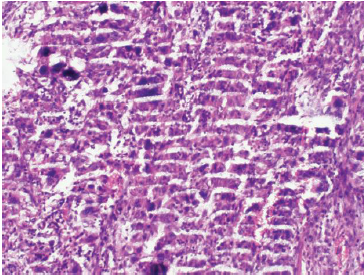

七、切片染色效果不佳

切片染色效果不佳可能是由于染色時(shí)間過長(zhǎng)或過短、染色液濃度不合適等原因造成的。

為了改善染色效果,我們可以按照以下步驟進(jìn)行調(diào)整:

①根據(jù)實(shí)驗(yàn)需要,選擇合適的染色液種類和濃度。

②控制染色時(shí)間,確保染色充分且不過度。